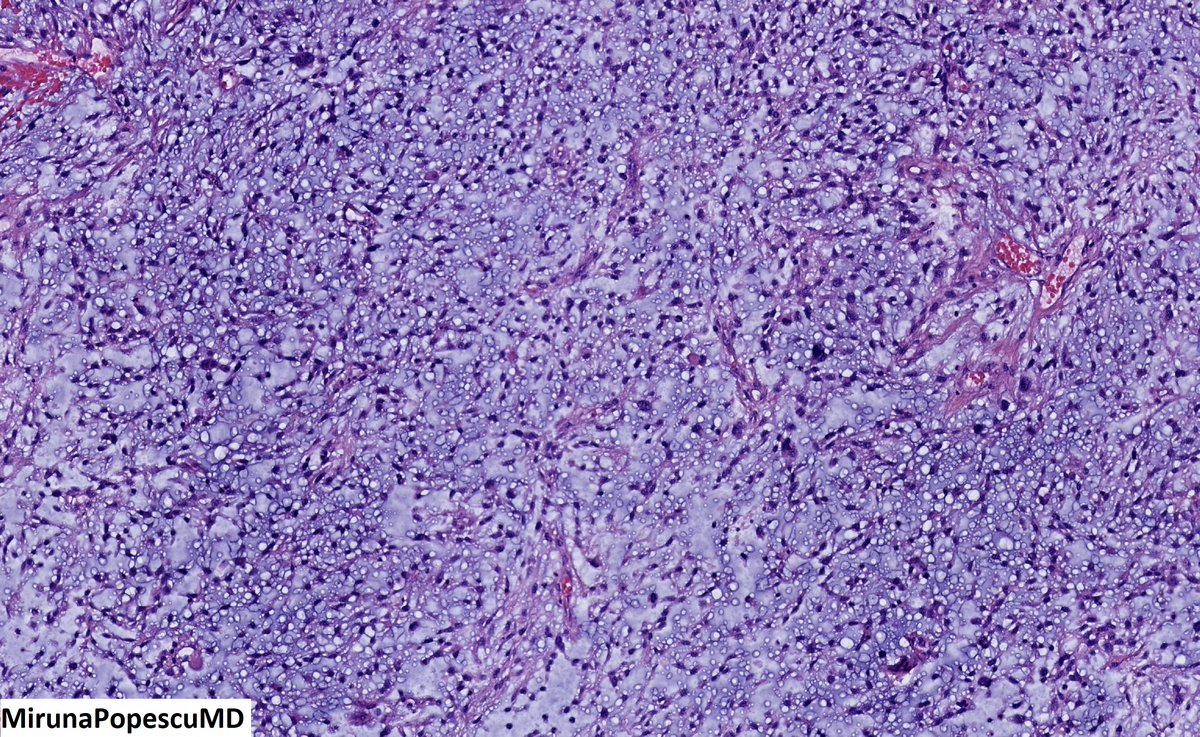

@MirunaPopescu13

❓ Let’s do a quick #BSTPath quiz ❓ 60 y/o F with a retroperitoneal mass 🔪 Follow the 🧵 👇🏽 for the answers & for a short tweetorial (1/11) #PathTwitter #pathoutpic #pathtweetorial